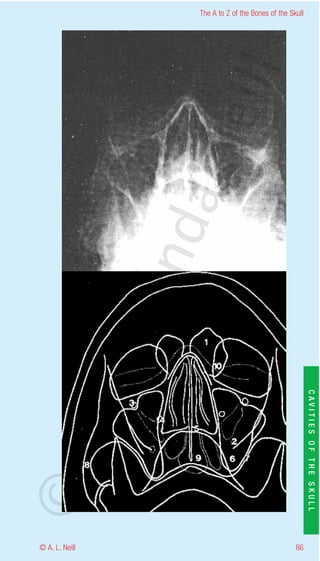

The A to Z of the Bones of the Skull

Orbital cavity Inferoanterior

eill

radiology (also Orbital fossa Optic cavity Optic foramen)

1           Frontal sinus

2           Foramen ovale

3           Infraorbital foramen

aN

4           Foramen rotundum

5           Hard palate –floor of nasal cavity

6           Maxillary antrum

7           Lateral wall of maxillary antrum

8           Zygomatic arch

9           Sphenoid sinus

nd

10          Soft tissue of nose and lower lid

ma

rA

CAVITIES OF THE SKULL

©D

85                                                         © A. L. Neill